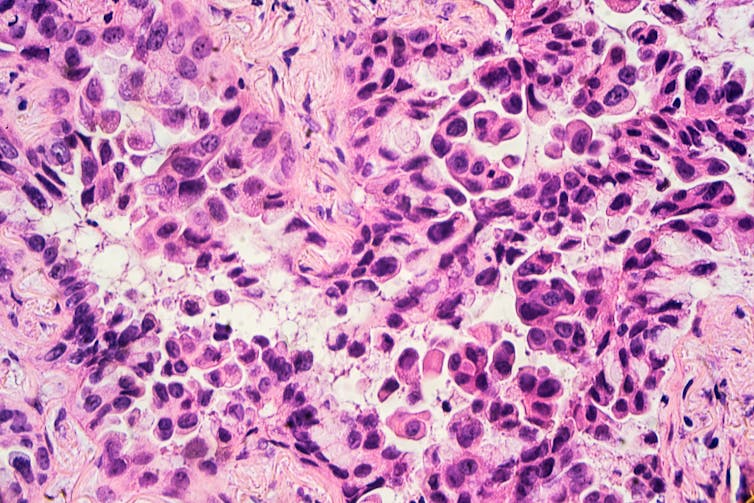

However, the proofreader occasionally fails. And on rare instances, these mutations occur in parts of the DNA called oncogenes. Under normal conditions, oncogenes are essential to normal growth and development, such as fetal organ development and general tissue repair and maintenance. But when mutations cause oncogenes to signal for unregulated growth, cancer can form.

One way to kill these tumor cells is to use targeted therapy. Cancer-targeted therapies bind specifically to the defective proteins produced by mutated oncogenes and prevent them from sending a “grow” signal.

Because targeted therapies bind directly to the cancerous protein, they spare most noncancerous cells from being harmed. This results in more specific cancer cell killing and less overall treatment toxicity. In contrast, chemotherapy attacks all actively dividing cells, which includes not just cancer but also hair follicles, the digestive tract and other parts of the body.